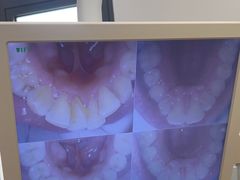

• 圣贝口腔(海淀店)

• -圣贝口腔(海淀店)